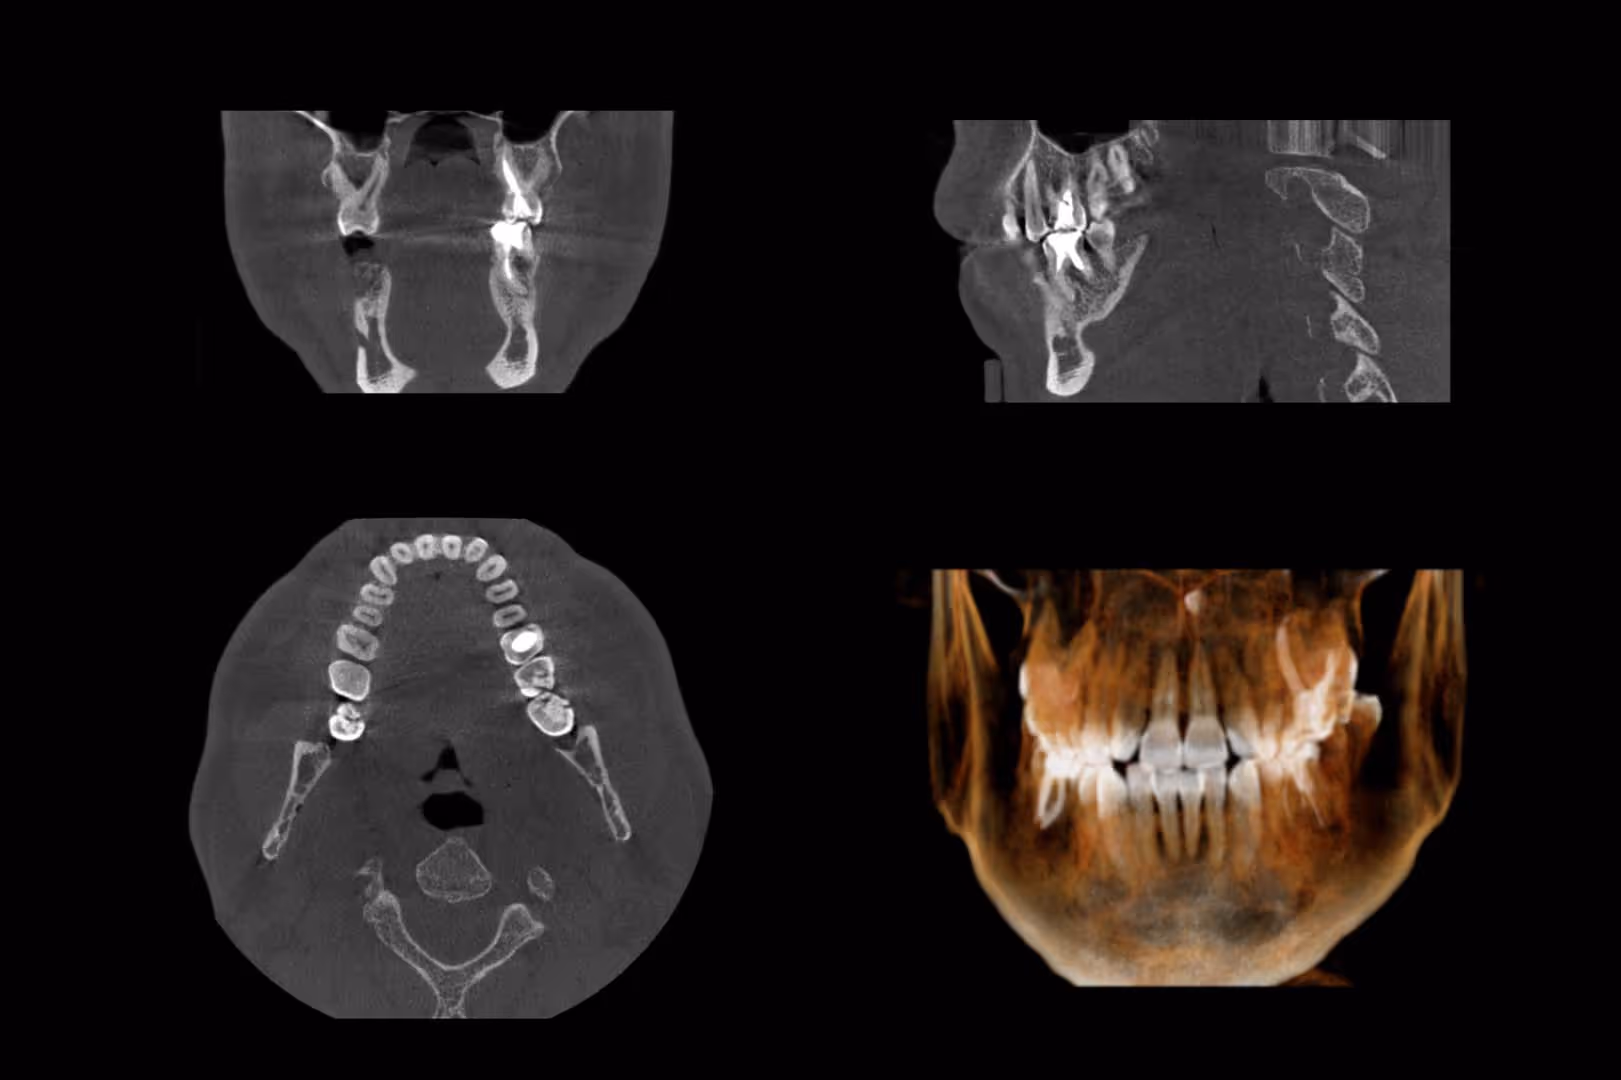

A cone beam CT scan involves a special type of x-ray that allows us to see the details of your oral and facial health. This scan is more than just a typical x-ray, since it allows us to identify nerve pathways, soft tissue and bone before providing you with treatment. This gives us a clear view of your oral health so that treatment is easier and more effective for you. The scan takes just seconds in our office and provides us with a highly detailed image.